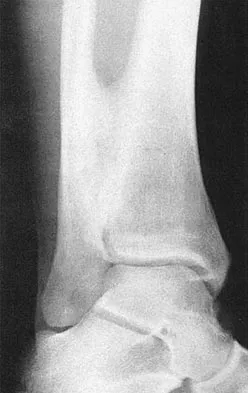

A 22-year-old professional ballet dancer reports a 3-month history of posterior ankle pain that occurs when she changes from a flat foot to pointe (hyperplantar flexed position). Examination does not elicit the pain with forced passive plantar flexion. A radiograph is shown in Figure 8. What is the most likely cause of the pain?

Correct Answer: Flexor hallucis longus tenosynovitis

Explanation:

The most common causes of posterior ankle pain in ballet dancers are flexor hallucis longus tenosynovitis and os trigonum syndrome. Flexor hallucis longus tenosynovitis differs from a symptomatic os trigonum by the absence of pain with forced plantar flexion and the presence of pain with resisted plantar flexion of the great toe. The pain is often felt in the posterior ankle and can be associated with a snapping or triggering sensation. Os trigonum syndrome commonly occurs in ballet dancers who perform in a position of extreme plantar flexion. The pain occurs from entrapment of the os trigonum between the posterior portion of the talus and calcaneus. Hamilton WG, Geppert MJ, Thompson FM: Pain in the posterior aspect of the ankle in dancers: Differential diagnosis and operative treatment. J Bone Joint Surg Am 1996;78:1491-1500.